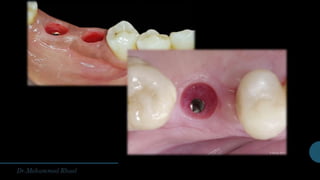

TWO sTAGE IMPLANT PLACEMENT

Also known as the “submerged” or “delayed” approach

The implant was inserted in a first surgery and submerged for three to six months to permit osseointegration.

In a second surgical procedure, the implant was exposed, its cover screw removed, and the implant was then

fitted with an abutment and the prosthetic phase of treatment was completed.

The two-stage approach is sometimes uncomfortable for the patient but has a proven record of success over

time

It continues to be a valuable surgical option when primary stability cannot be achieved, or if extensive pre-

surgical or concurrent bone augmentation is required